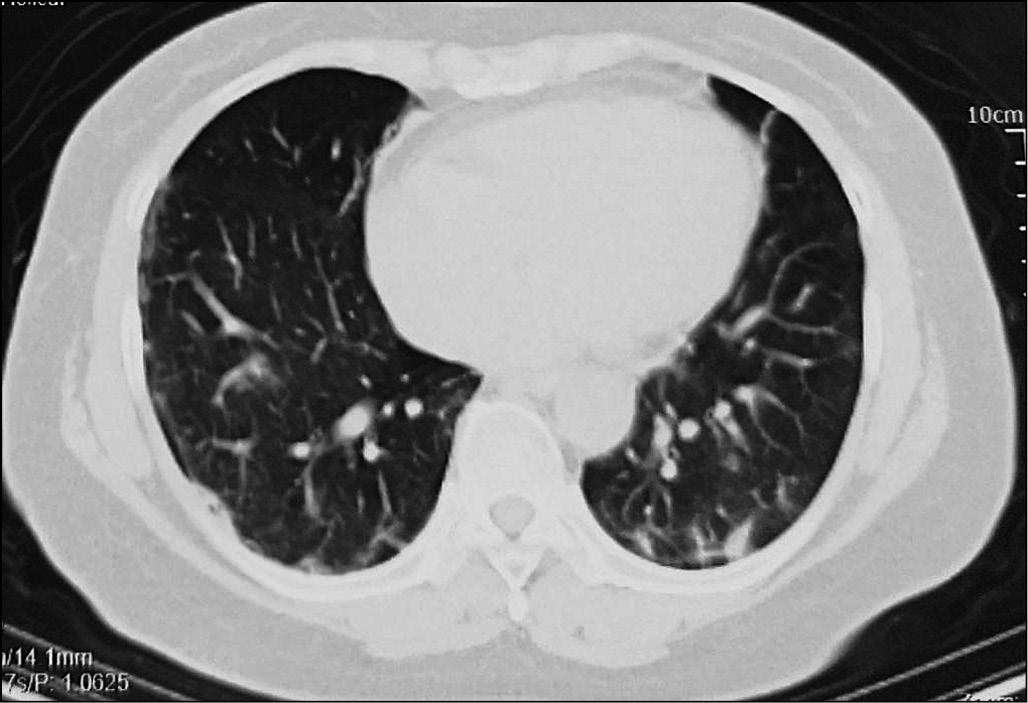

Компьютерная томография. Всего за время исследования получено 115 результатов КТ лёгких. По первым КТ-изображениям, выполненным до лечения, у 45,3% пациентов выявлен симптом «матового стекла», у 65,6% — бронхит, у 21,9% — фиброз, у 14,1% — кальциноз, у 12,5% — узловые образования. У 2 пациентов обнаружено утолщение плевры, у 3 — каверна лёгкого, у 2 — застарелый туберкулёз лёгких. Согласно результатам, между двумя возрастными группами не найдено статистически значимого различия по большей части поражений (p > 0,05); табл. 1, рис. 1–3.

Рис. 2. Фиброз и кальциноз в лёгком.